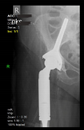

The radiological examination allowed us to verify the close bone-to-implant contact and the unchanged position of the implant during follow-up.

In all the cases operated with the above-described targeting procedure, the stems of the cups remained between the cortical bone surfaces without perforation of the linea terminalis, as shown by postoperative radiographs. There were no complicated surgical situations. In 16 cases, the wound healings were uneventful, and the hips were able to bear weight again after postoperative rehabilitation.